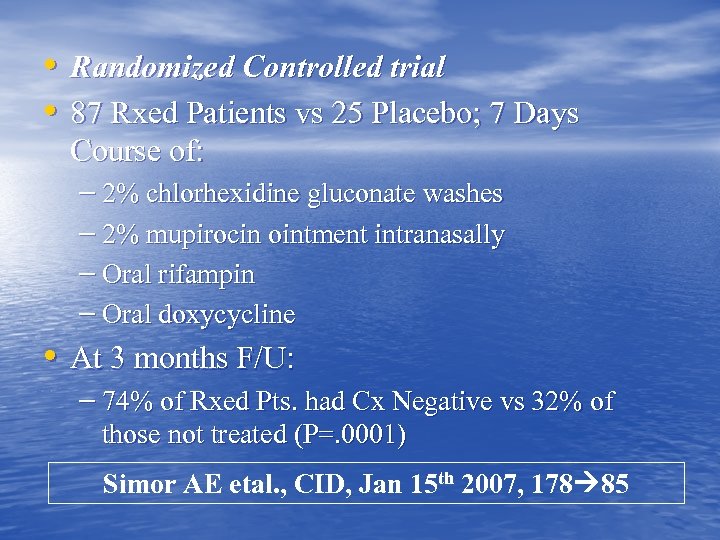

• Randomized Controlled trial • 87 Rxed Patients vs 25 Placebo; 7 Days Course of: – 2% chlorhexidine gluconate washes – 2% mupirocin ointment intranasally – Oral rifampin – Oral doxycycline • At 3 months F/U: – 74% of Rxed Pts. had Cx Negative vs 32% of those not treated (P=. 0001) Simor AE etal. , CID, Jan 15 th 2007, 178 85

• Randomized Controlled trial • 87 Rxed Patients vs 25 Placebo; 7 Days Course of: – 2% chlorhexidine gluconate washes – 2% mupirocin ointment intranasally – Oral rifampin – Oral doxycycline • At 3 months F/U: – 74% of Rxed Pts. had Cx Negative vs 32% of those not treated (P=. 0001) Simor AE etal. , CID, Jan 15 th 2007, 178 85